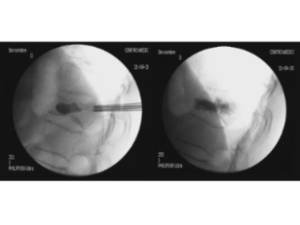

Percutaneous stabilization of unstable vertebral fractures

In cases of complex (unstable, burst, etc.) vertebral fractures, additional stabilization of the fracture by percutaneous stabilization is usually required. In cases where there also is a neurological deficit (muscle weakness, tingling in legs or arms, etc.), a decompression of the spinal canal is additionally required. A percutaneous stabilization of the spine with screws and rods discharges the load on the unstable fracture, stabilizing the whole spine and relieving pain. Depending on the patient’s bone quality, the stabilized vertebrae may be additionally cemented by kyphoplasty.